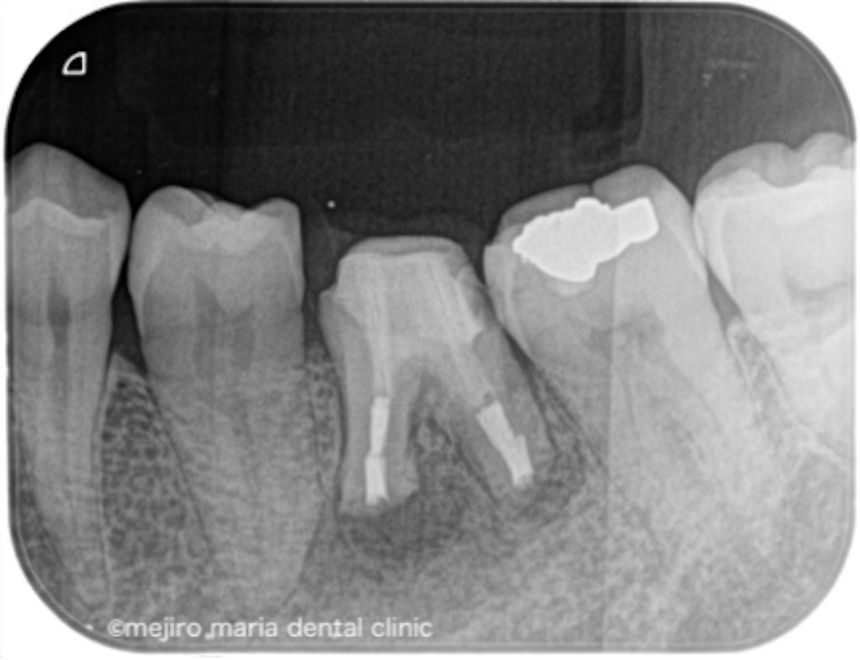

術後3ヶ月の経過観察では、歯肉の腫れや噛んだときの違和感、痛みは消失し予後良好と判断しました。引き続き最終補綴処置(被せ物)の製作を行い2年間の経過観察に移行することとなりました。

今回の症例は長期間病状を放置してしまった結果、根管の外に歯石が形成され、根管治療のみで治癒させることができず、次いで歯根端切除術を行うことで治癒に導いた症例です。